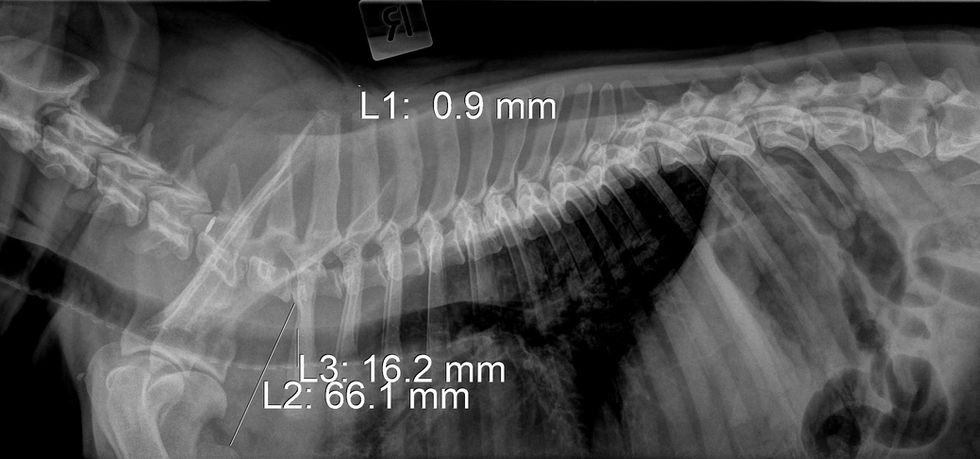

Below is copies of his reports, X-rays, general photos and videos.